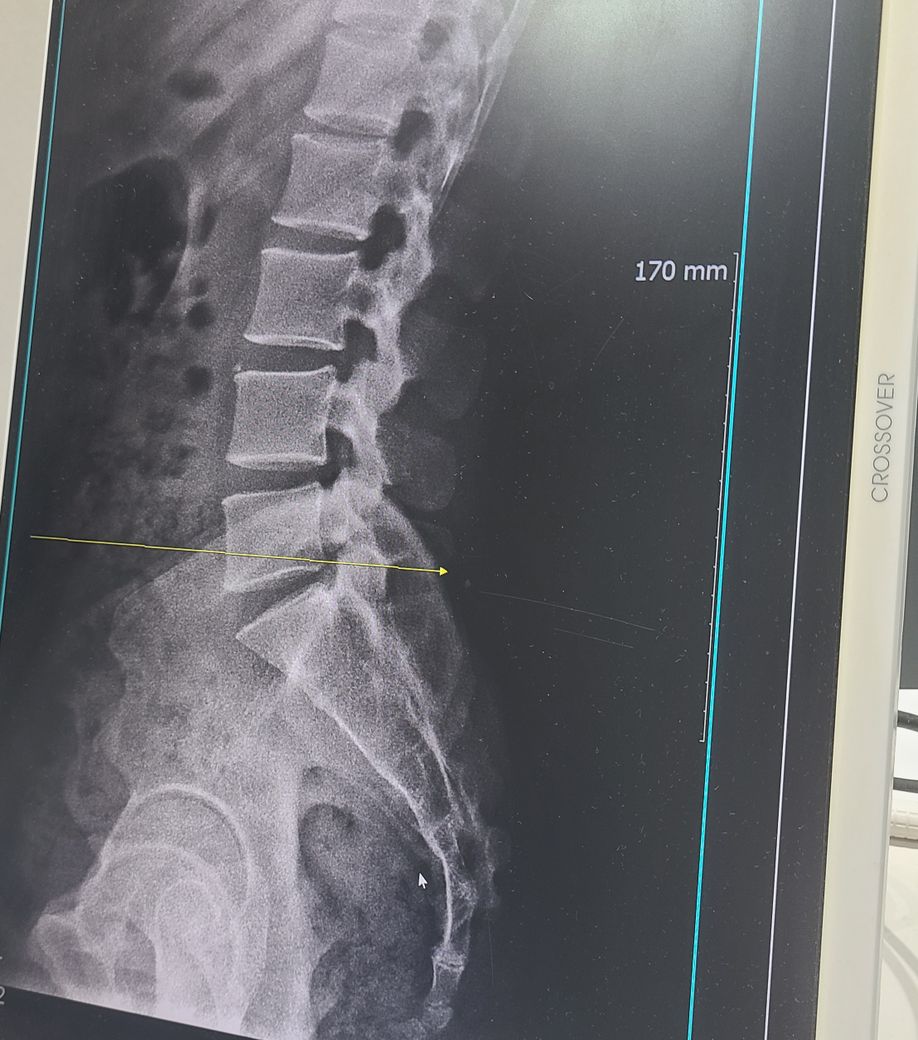

5번 척추와 꼬리뼈 사이 틈이 좁아졌는데 어떤 자세가 좋을까요

치료는 받는중인데 궁금한게 생겨서 보통 허리는 S자를 유지하라고 하는데 S자가 너무 심해져서 꼬리뼈가 쳐진거 같아서요 이럴경우 앉은자세를 오히려 C자로 되게 만드는게 좋을까요 꼬리뼈를 좀더 펴줘야 될꺼같은데 이게 맞는건지 궁금해요

5번 척추와 꼬리뼈 사이 틈이 좁아졌다면 올바른 자세르 유지하는 것이 중요합니다. 허리를 S자로 형태로 유지하는 것이 일반적으로 좋지만 너무 과도하면 오히려 꼬리뼈에 부담을 줄 수 있습니다 앉을 때 자연스럽게 허리를 펴고 약간의 C자 형태를 유지하면서 골반을 중립 위치로 두는 것이 좋습니다. 전문의와 상담해 개인에 맞는 자세교정을 받는 것도 도움이 될 수 있어요!